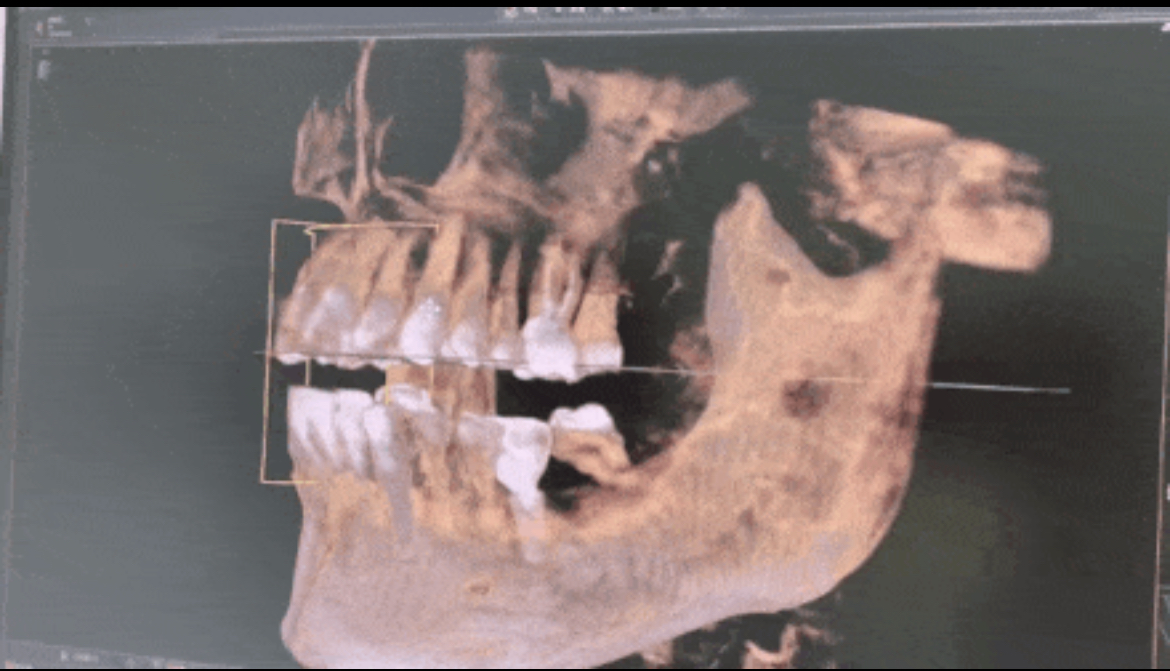

在海德堡联合口腔植入骨粉前会根据Sirona CBCT全景影像片设备得出的数据严格分析牙槽骨骨量的密度、高度等,做到精确,再精确!

■首先患者只需要通过CBCT进行全面扫描,可以显示出三维口腔结构,再通过3shape口扫对患者的口腔信息进行数字化采集。包括患者牙槽骨厚薄、高低,甚至血管神经的精确位置。

▲CBCT可以得到三维图像,更加直观精准

将两次图像进行拟合比对,很快就能找到适合种植的牙槽骨位置和种植位点。